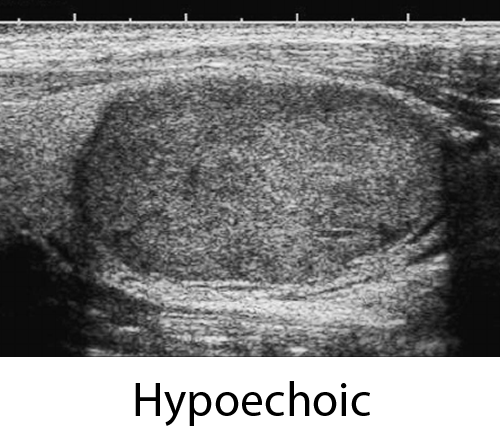

ECHOGENICITY --

Selected Echogenicity:

Anechoic (0 points)